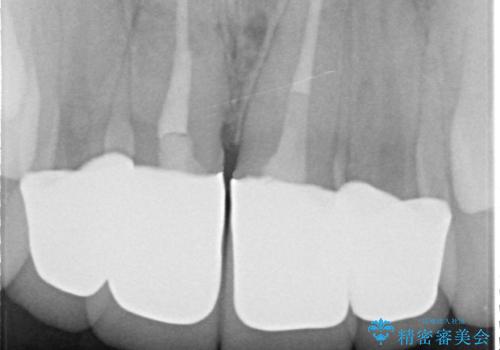

- 上顎前歯の歯並びが気になるが仕事が忙しく矯正治療は難しいため、セラミック矯正で綺麗にしたいといらっしゃった方の症例です。

左右の1番目の歯は傾きが大きいため、セラミッククラウンにするにあたり神経治療を行うことを御了承頂いた上で、前歯4本をオールセラミッククラウン(スペシャル)により補綴しました。